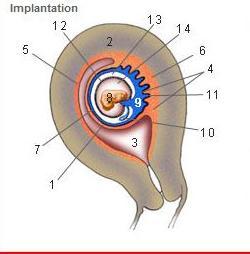

The placenta is composed of two components, what are they?

tissue from both mother and fetus

What is the fetal part of the placenta called?

Chorionic plate

chorion frondosum

What is the maternal part of the placenta called?

Decidua basalis

endometrial surface

What is the Decidua?

uterine lining (endometrium) during a pregnancy, which forms the

maternal part of the placenta.

What causes decidualize?

influence of hormones

Where is the Desidua Capsularis?

1

Where is the Desidua basalis?

6

Where is the Desidua parietalis?

5

Where is the chorion frondosum?

11

Where is the amnion?

12

Where is the chorionic cavity?

13

What is the chorionic villi?

functioning unit of the placenta

finger-like structures containing one fetal blood

capillary per villi

Where are the chorionic villi located?

intervillious space

What is the chorionic villi responsible for?

exchange of:

nutrients

waste

oxygen

carbon dioxide